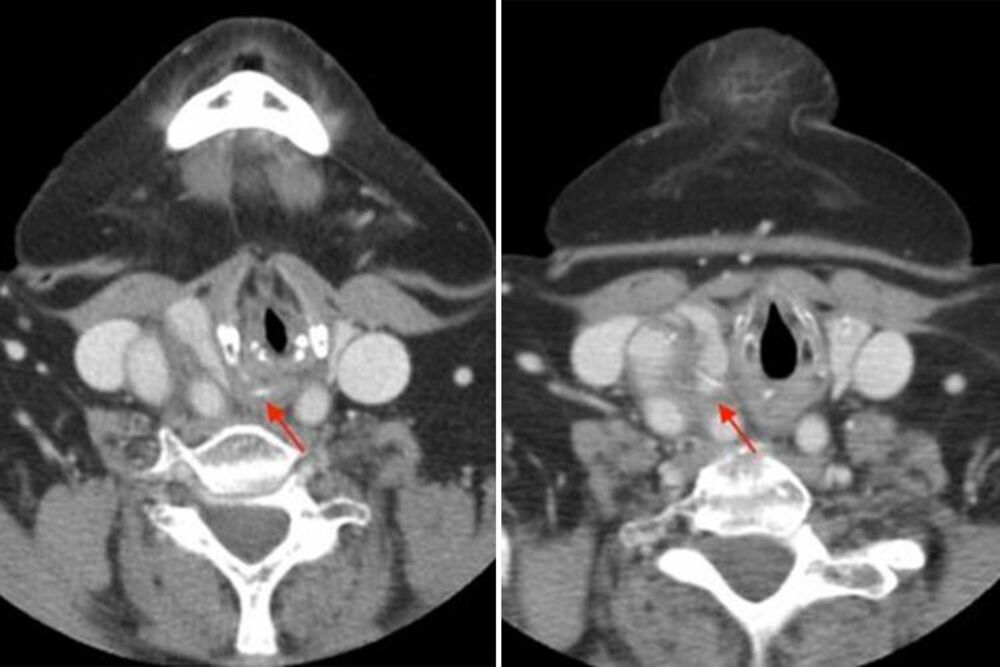

Analiza slučaja objavljena u “International Journal of Surgery Case Reports” navodi da je 61-godišnji muškarac umro nakon što mu se riblja kost veličine centimetra zaglavila u tankom crevu. Izazvala je infekciju, a muškarac se zbog nepodnošljivih bolova u stomaku, povraćanja i zatvora obratio lekarima.

Ubrzo je smešten na intenzivnu negu, gde je lečen antibioticima i infuzijom, a posle toga, lekari su pronašli riblju kost dugačku centimetar. Muškarac je odmah poslat na operaciju, kada su doktori ustanovili da je kost probila crevo, što je dalje uzrokovalo infekciju.

U slučaju 61-godišnjeg muškarca, lekari su uklonili oko 10 centimetara creva, ali pacijent se nije oporavljao. Posle osam sati, muškarac je doživeo srčani udar i preminuo.